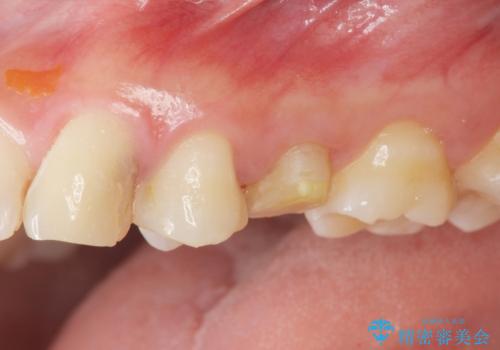

- 歯ぐきの腫れや、歯の内部が黒く見えることからの虫歯の治療を求めて来院されました。

虫歯が大きかったことから、神経の温存はできたものの歯ぐきよりも深い虫歯の問題を解決するため、部分矯正治療を併用したセラミック治療を行うこととしました。

当初、歯ぐきよりも深い虫歯の存在や、歯のポジションに問題がありましたがマルチブラケットを用いた部分矯正で行うことで歯の挺出同時に適切な位置へと歯を移動させ、歯周環境を整えたセラミック治療を行うことができました。